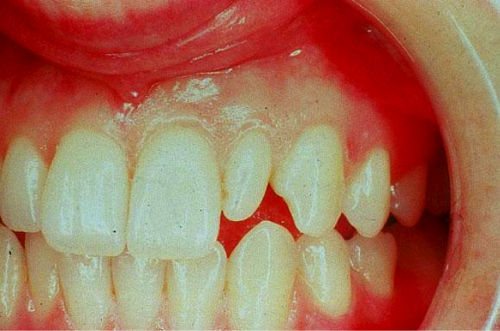

Макродентия характеризуется увеличенным размером коронковой части зубов. Этот тип отклонения гораздо опаснее для здоровья человека, чем микродентия. Состояние считается нормой только в том случае, если пациент имеет развитые челюстные структуры, в противном случае патология влечет за собой смещение единиц ряда и нарушение прикуса.

Стоматологи выделяют 2 вида макродентии: локализованную и генерализованную. При локализованном типе увеличено несколько элементов при генерализованной форме дефекта величина всех зубов превышает нормальные значения.

Макродентия – увеличенные зубы. Бывает у верхних резцов или боковых. Реже – на нижней челюсти, спереди. Превышение диагностируется при осмотре стоматологом, размеры его определяются при сравнении данных пациента со среднестатистическими. Оно может достигать диапазона 2–6 мм.

При диагностировании проверяют следующие размеры зуба: длину, ширину, высоту коронки. Ширина определяется измерением в самой широкой части зубного тела, высоту – от края десны пришеечной части до острого края или бугорка на жевательной поверхности. Макродентия на одной из челюстей вызывает диспропорции и нарушение прикуса.

Патологические размеры подразумевают слишком большие или слишком мелкие зубы. В первом случае налицо диагноз макродентия, который означает увеличенный размер коронки. Такая проблема приводит к трудностям с прорезыванием остальных «соседей», скученности и неправильному положению. Это косметическая патология, которая портит внешность. Лечение заключается в удалении и исправлении формы остальных зубов. Также проводится протезирование с целью закрытия дефектов.